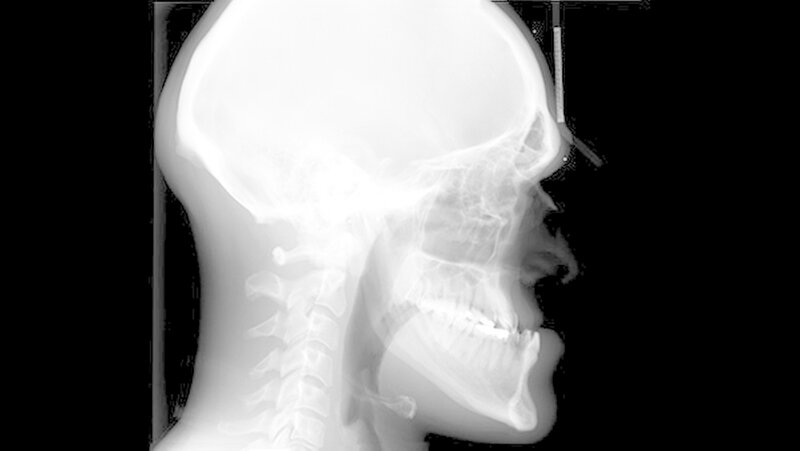

Der Fall: Progenie durch Akromegalie

Hintergrund: Die Akromegalie ist eine endokrinologische Erkrankung, die durch eine Überproduktion des Wachstumshormons Somatropin hervorgerufen wird. Ein Hormon-produzierendes Adenom - das ist ein gutartiger Tumor - an der Hypophyse ist in den meisten Fällen die Ursache dieser Erkrankung.

Am Gesichtsschädel führen die Wachstumshormone zu einem persistierenden Wachstum des Unterkiefers. Die Körperproportionen erscheinen dadurch extrem unharmonisch und vergröbert. Der daraus entstehende Fehlbiss ist häufig auch verantwortlich für degenerative Kiefergelenkserkrankungen.